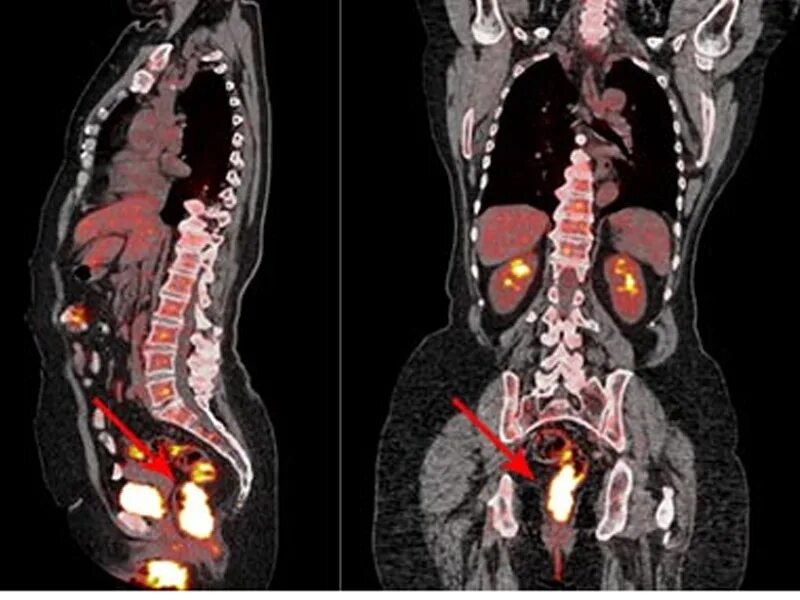

Пэт кт онкобольным